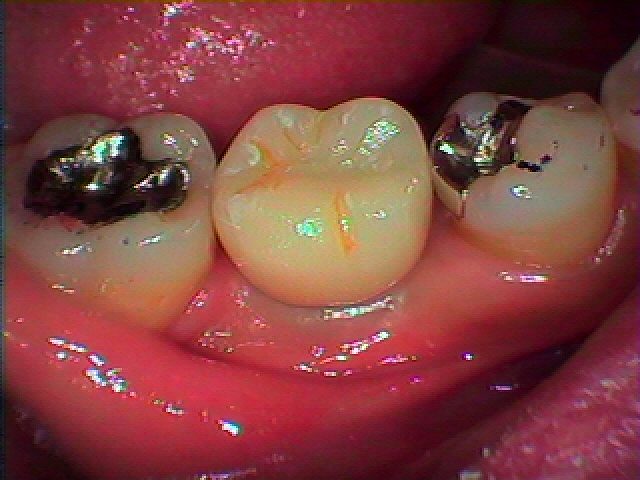

セレックオールセラミックにて上部構造を作成しています

汚れがセラミックはつきにくいのとジルコニアのように割れない

マテリアルよりも、過大な咬合圧にて割れてブレーキがかかるオールセラミックをインプラントには採用しています

何十年ももつ装置がゆえにそのように作成しています